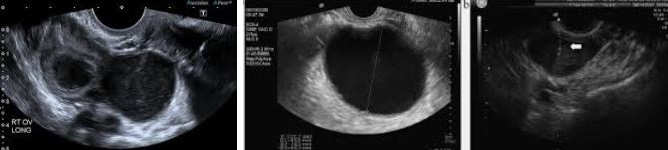

Ovarian endometriosis causes the adhesions between the ovarian surface and the broad ligament. As the ovary enlarges, endometriomas form. Sometimes surface endometrial implants penetrate more deeply into the cyst wall, making excision more difficult. The degree of endometrial invasion of the cyst wall forms the basis for differentiating between these two subtypes and is characterized by the progressive difficulty in removing the cyst wall.